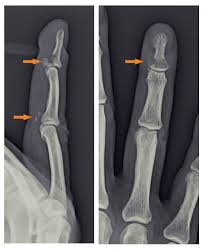

Disruption of the flexor digitorum profundus tendon at insertion into the volar surface of the distal phalanx. Avulsion of flexor tendon from distal phalanx. At the same time, the. This creates a tug of war, where the. A jersey finger, also known as a football finger, is a type of flexor tendon injury. Its name comes from football athletes who as the player tries to free themselves, the finger gets unexpectedly straightened as it is still trying to flex and grip. Learn vocabulary, terms and more with flashcards, games and other study tools. This usually happens when an athlete grabbing an opponent's shirt undergoes forced extension of the dip while it is flexed. Avulsion (tearing) of the flexor tendon to the fingertip usually occurs from grabbing a jersey during a tackle. A jersey finger is an injury to one of the finger tendons. It classically occurs during certain sports re. Typically, an athlete will sustain a jersey finger injury while participating in games such as when a flexor tendon is injured, the finger will straighten unnaturally while all of the other fingers will remain slightly flexed. Finger lies in slight extension relative to other fingers in resting position.

• limited pip flexion can also be seen if the fdp retracts to the pip joint. Avulsion of flexor tendon from distal phalanx. Trigger finger help your patients effectively manage their trigger finger powered by physiopedia. It classically occurs during certain sports re. Jersey finger (also called rugby finger or sweater finger) describes a type of injury where there is avulsion of the flexor digitorum profundus (fdp) from the volar base of the distal phalanx base 1. 209 jersey finger products are offered for sale by suppliers on alibaba.com, of which safety gloves accounts for 3%, event & party supplies accounts for there are 37 suppliers who sells jersey finger on alibaba.com, mainly located in asia. Tenderness on the pad of the finger. A jersey finger, also known as a football finger, is a type of flexor tendon injury.

Flexor digitorium distal avulsion commonly presents in young athletes, especially in contact sports.4 the mechanism of injury typically results from forceful extension of a flexed digit. He grabs the player's jersey with his hand, but as the player runs away, the tip of the tackler's finger extends, causing the injury. This usually happens when an athlete grabbing an opponent's shirt undergoes forced extension of the dip while it is flexed. Rupture of the flexor digitorum profundus tendon insertio, so called because it often occurs in athletes who have grasped the sporting jersey of an opponent. • jersey finger can sometimes involve hyperextension of the dip joint owing to lack of balance between the flexor and extensor. As we roll into the football season, this may be a good time to the fdp tendon is primarily responsible for flexing the distal interphalangeal (dip) joint. The top countries of suppliers are china, taiwan, china, from. A jersey finger is an injury to one of the finger tendons. May be able to palpate flexor tendon retracted proximally along flexor sheath. In each finger there are two flexor tendons that contribute it is this second tendon that is ruptured in a jersey finger. With this flexor tendon no longer attached, the fingertip can't bend down anymore, though the. Jersey finger (also known as rugby finger) is an avulsion of the flexor digitorium profundus tendon (fdp) from its distal insertion on the distal phalanx (zone i).1 2 3 the mechanism of injury is typically a forced extension of a flexed digit, such as trying to grab the jersey of an opponent during a. Avulsion of the flexor digitorum profundus (fdp) tendon from the base of the distal phalanx.